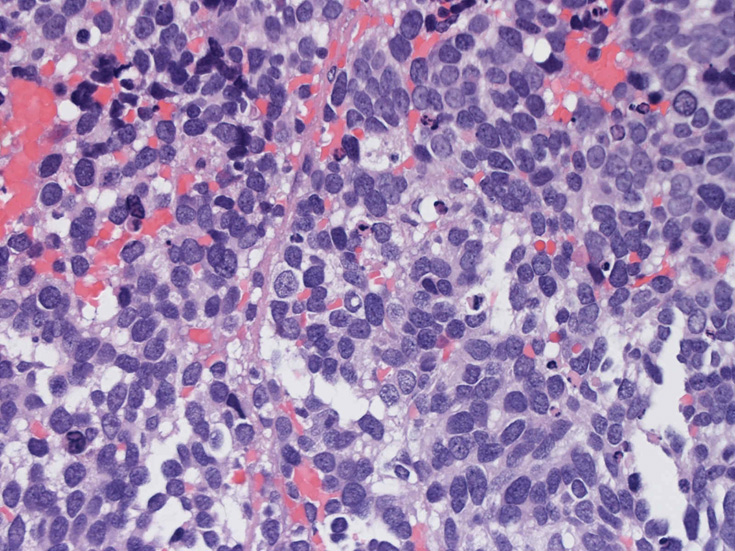

Alveolar rhabdomyosarcoma 胞巣型横紋筋肉腫(ARMS)

組織像

30歳代男性 鼻腔腫瘤の生検組織

厳密にはalveolar patternが明らかではなく, solid typeに入る症例かもしれない。異型細胞増殖胞巣が線維化組織に取り囲まれるように散在している. 小さな生検組織のため全体像が不明である。